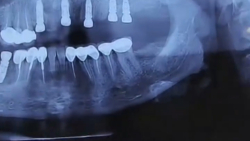

ایمپلنت فک پایین